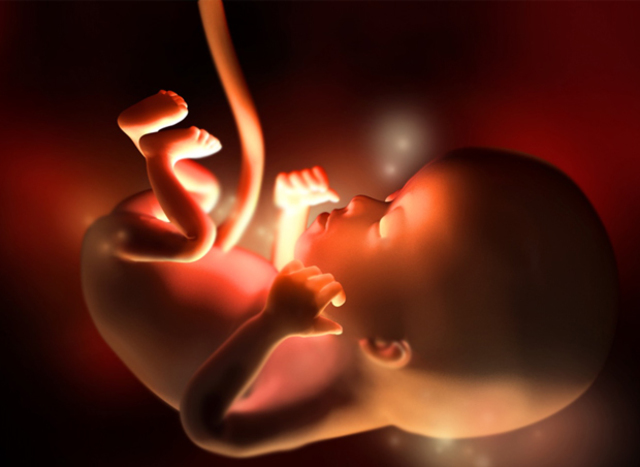

• SEMANA 30

SEMANA 30

Su cerebro ha crecido y se acomoda al tamaño de su cabeza, sus pulmones continúan madurando, comienza a buscar la posición definitiva que tendrá al nacer.